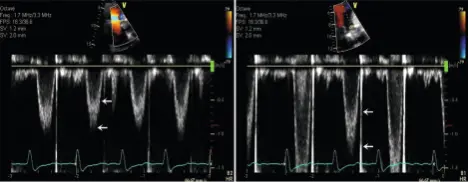

- Caption from Figure 4-6 of Oh Textbook: Examples of LVOT PWD velocity recording in a patient with atrial fibrillation. The sample volume needs to be placed about 5 mm from the aortic annulus to avoid flow acceleration. The spectral broadening (interval between two arrows with turbulent flow) should be less than 40 cm/s (left). The sample volume is too close to the aortic valve or too large in the example shown (right). Of note, there is some variation of LVOT velocity in this example because of atrial fibrillation.

- From the Apical 5-Chamber (A5C) view, the sample volume is placed in the LVOT within 5 mm of the aortic annulus to avoid the flow acceleration.

- Normal values for LVOT peak velocity: 0.9 to 1.1 m/s

- Normal values for TVI: 20 to 24 cm.